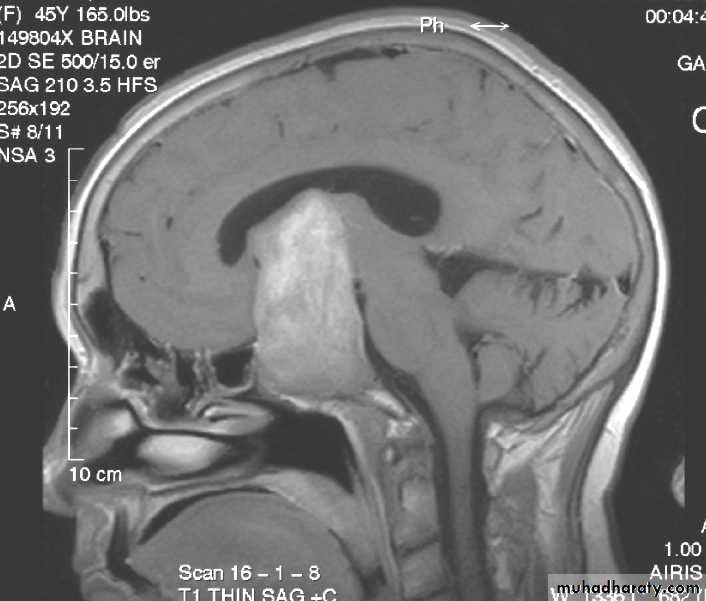

• 3. Magnetic Resonance Imaging (MRI): same as CT• 4. Angiography: Used to evaluate the blood supply and vasculature of the tumor.

• Non-functioning pituitary adenomas• Functioning pituitary adenomas

Non-functioning pituitary adenomas

• Accounts for about 30% of pituitary tumours.

• They are often seen in the fourth and fifth decades of life.

• Because they are non-functioning, they are not generally diagnosed until they are very large.

• Their presentation is by optic chiasm compression that cause visual field defect (bitemporal hemianopia).

• The usual treatment is microscopic trans-sphenoidal or trans-cranial excision.

Functioning pituitary adenomas

• Pituitary adenomas are classified according to the hormones they secrete. They include:• Prolactin secreting adenomas.

• Growth hormone secreting adenomas that produce acromegaly or gigantism.

• Glycoprotein secreting adenomas that produce excess amount of TSH, LH, or FSH.

• ACTH secreting adenomas that produce Cushing's disease.

• Some of these secrete more than one hormone, e.g. prolactin-growth hormone secreting adenomas.

• 2. Adenomas may be further divided according to their sizes into Microadenomas that are less than 1 cm in diameter, and Macroadenomas that have a larger size.• 3. Functioning adenomas are diagnosed by:

• Clinical changes.

• Hormone assessment. And

• Radiology by using MRI and CT scan.

6. Surgical excision can preferably done by using the trns-sphenoidal route, whether sublabial or transnasal, although transcranial approach can also be used.

7. In case of an invasive tumour with incomplete excision, radiotherapy is required